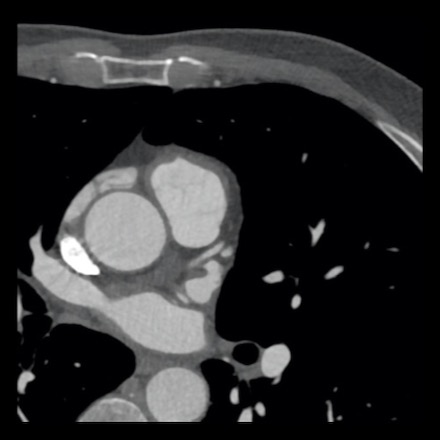

case 1 – CAD-RADS 2/P1

First, scroll through the scan.

Not all images are included. Some images without any abnormalities are skipped

from the series.

How would you describe the findings on the coronary CTA?

The findings are:

- Agatston score of

this patient was 14 (P1). Please, also note the calcification of the aortic valve. - Some partially

calcified and calcified plaques are present in the LAD with mild stenosis

(25-49%). - Calcified-plaque in

the LCX causing minimal stenosis (<25%). - Non-calcified

plaque in the distal RCA causing minimal stenosis (<25%). - This patient classifies

as CAD-RADS 2/P1, which means no further workup is needed.